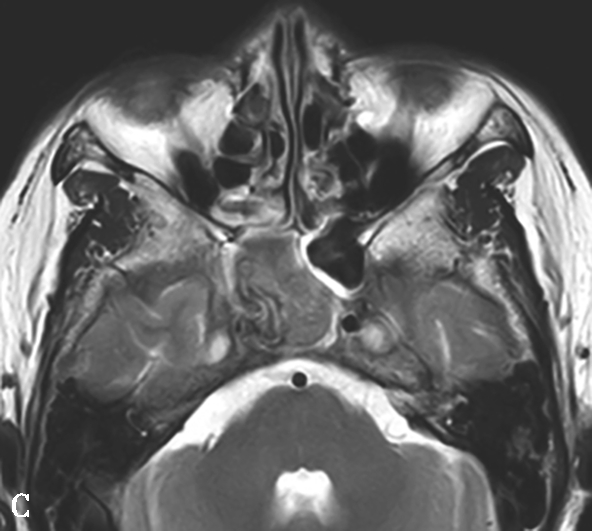

图1-3-26 鼻腔鼻窦肉芽肿性多血管炎

A、B.横断面CT及冠状面CT骨窗,示鼻背部塌陷,鼻中隔、双侧筛窦及上颌窦黏膜增厚,窦壁骨质增生硬化,内缘骨皮质欠光整;双侧中、下鼻甲形态欠自然,双侧眼眶内下壁骨皮质部分缺损,邻近内下象限肌锥外间隙可见弥漫性软组织增厚影,右侧为著;双侧上颌窦口-鼻道复合体增宽,钩突缺如;C.横断面T 1 WI,示双侧上颌窦腔可见略低信号,气-液平面可见,鼻背部塌陷,鼻中隔黏膜增厚,鼻咽顶后壁软组织增厚,呈等信号;D.横断面T 2 WI,示上颌窦腔病变呈高信号,余病变呈略低信号;E.横断面T 1 WI+FS+C,示窦腔、鼻中隔增厚,黏膜及其他受累结构呈中等强化,双侧翼腭窝及上颌窦后脂肪间隙受累,强化;F.冠状面T 1 WI+FS+C,示双侧眼眶内下象限肌锥外间隙病变呈中等强化,大脑纵裂及额部脑膜受累,呈弥漫性增厚强化